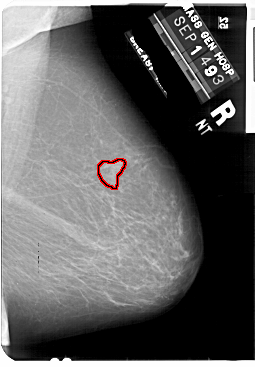

A_1858_1.RIGHT_MLO

RIGHT_MLO LINES 5491 PIXELS_PER_LINE 3811 BITS_PER_PIXEL 12 RESOLUTION 43.5 OVERLAY

FILE: A_1858_1.RIGHT_MLO.OVERLAY

TOTAL_ABNORMALITIES 1

ABNORMALITY 1

LESION_TYPE MASS SHAPE LOBULATED MARGINS ILL_DEFINED

ASSESSMENT 4

SUBTLETY 3

PATHOLOGY BENIGN

TOTAL_OUTLINES 1

BOUNDARY